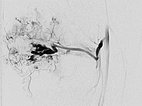

After renewed superselective catheterization of the AVM-feeding artery (lateral inferior genicular artery) ), the microcatheter is advanced to just before the nidus.

DSA image (roadmap technique) during re-embolization shows the freshly injected new additional embolic agent as black in the image.

Final DSA images (left AP, right lateral projection) after completion of repeat embolization again shows angiographically complete occlusion of both portions of the AVM.